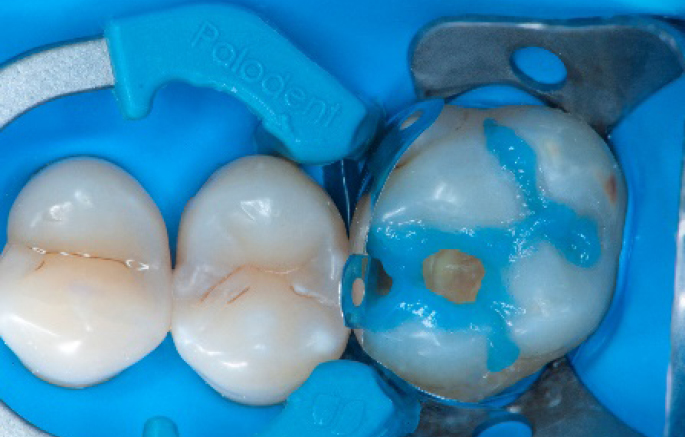

Step 6:

Selective enamel etching procedure with Conditioner2.

Step 8:

Transformation of class II into class I, restoring the interproximal wall with Spectra ST4 composite in shade A2.

Step 9:

Transformation of a big class I into a small class I, using SDR® flow+ material in one increment up to 4 mm.